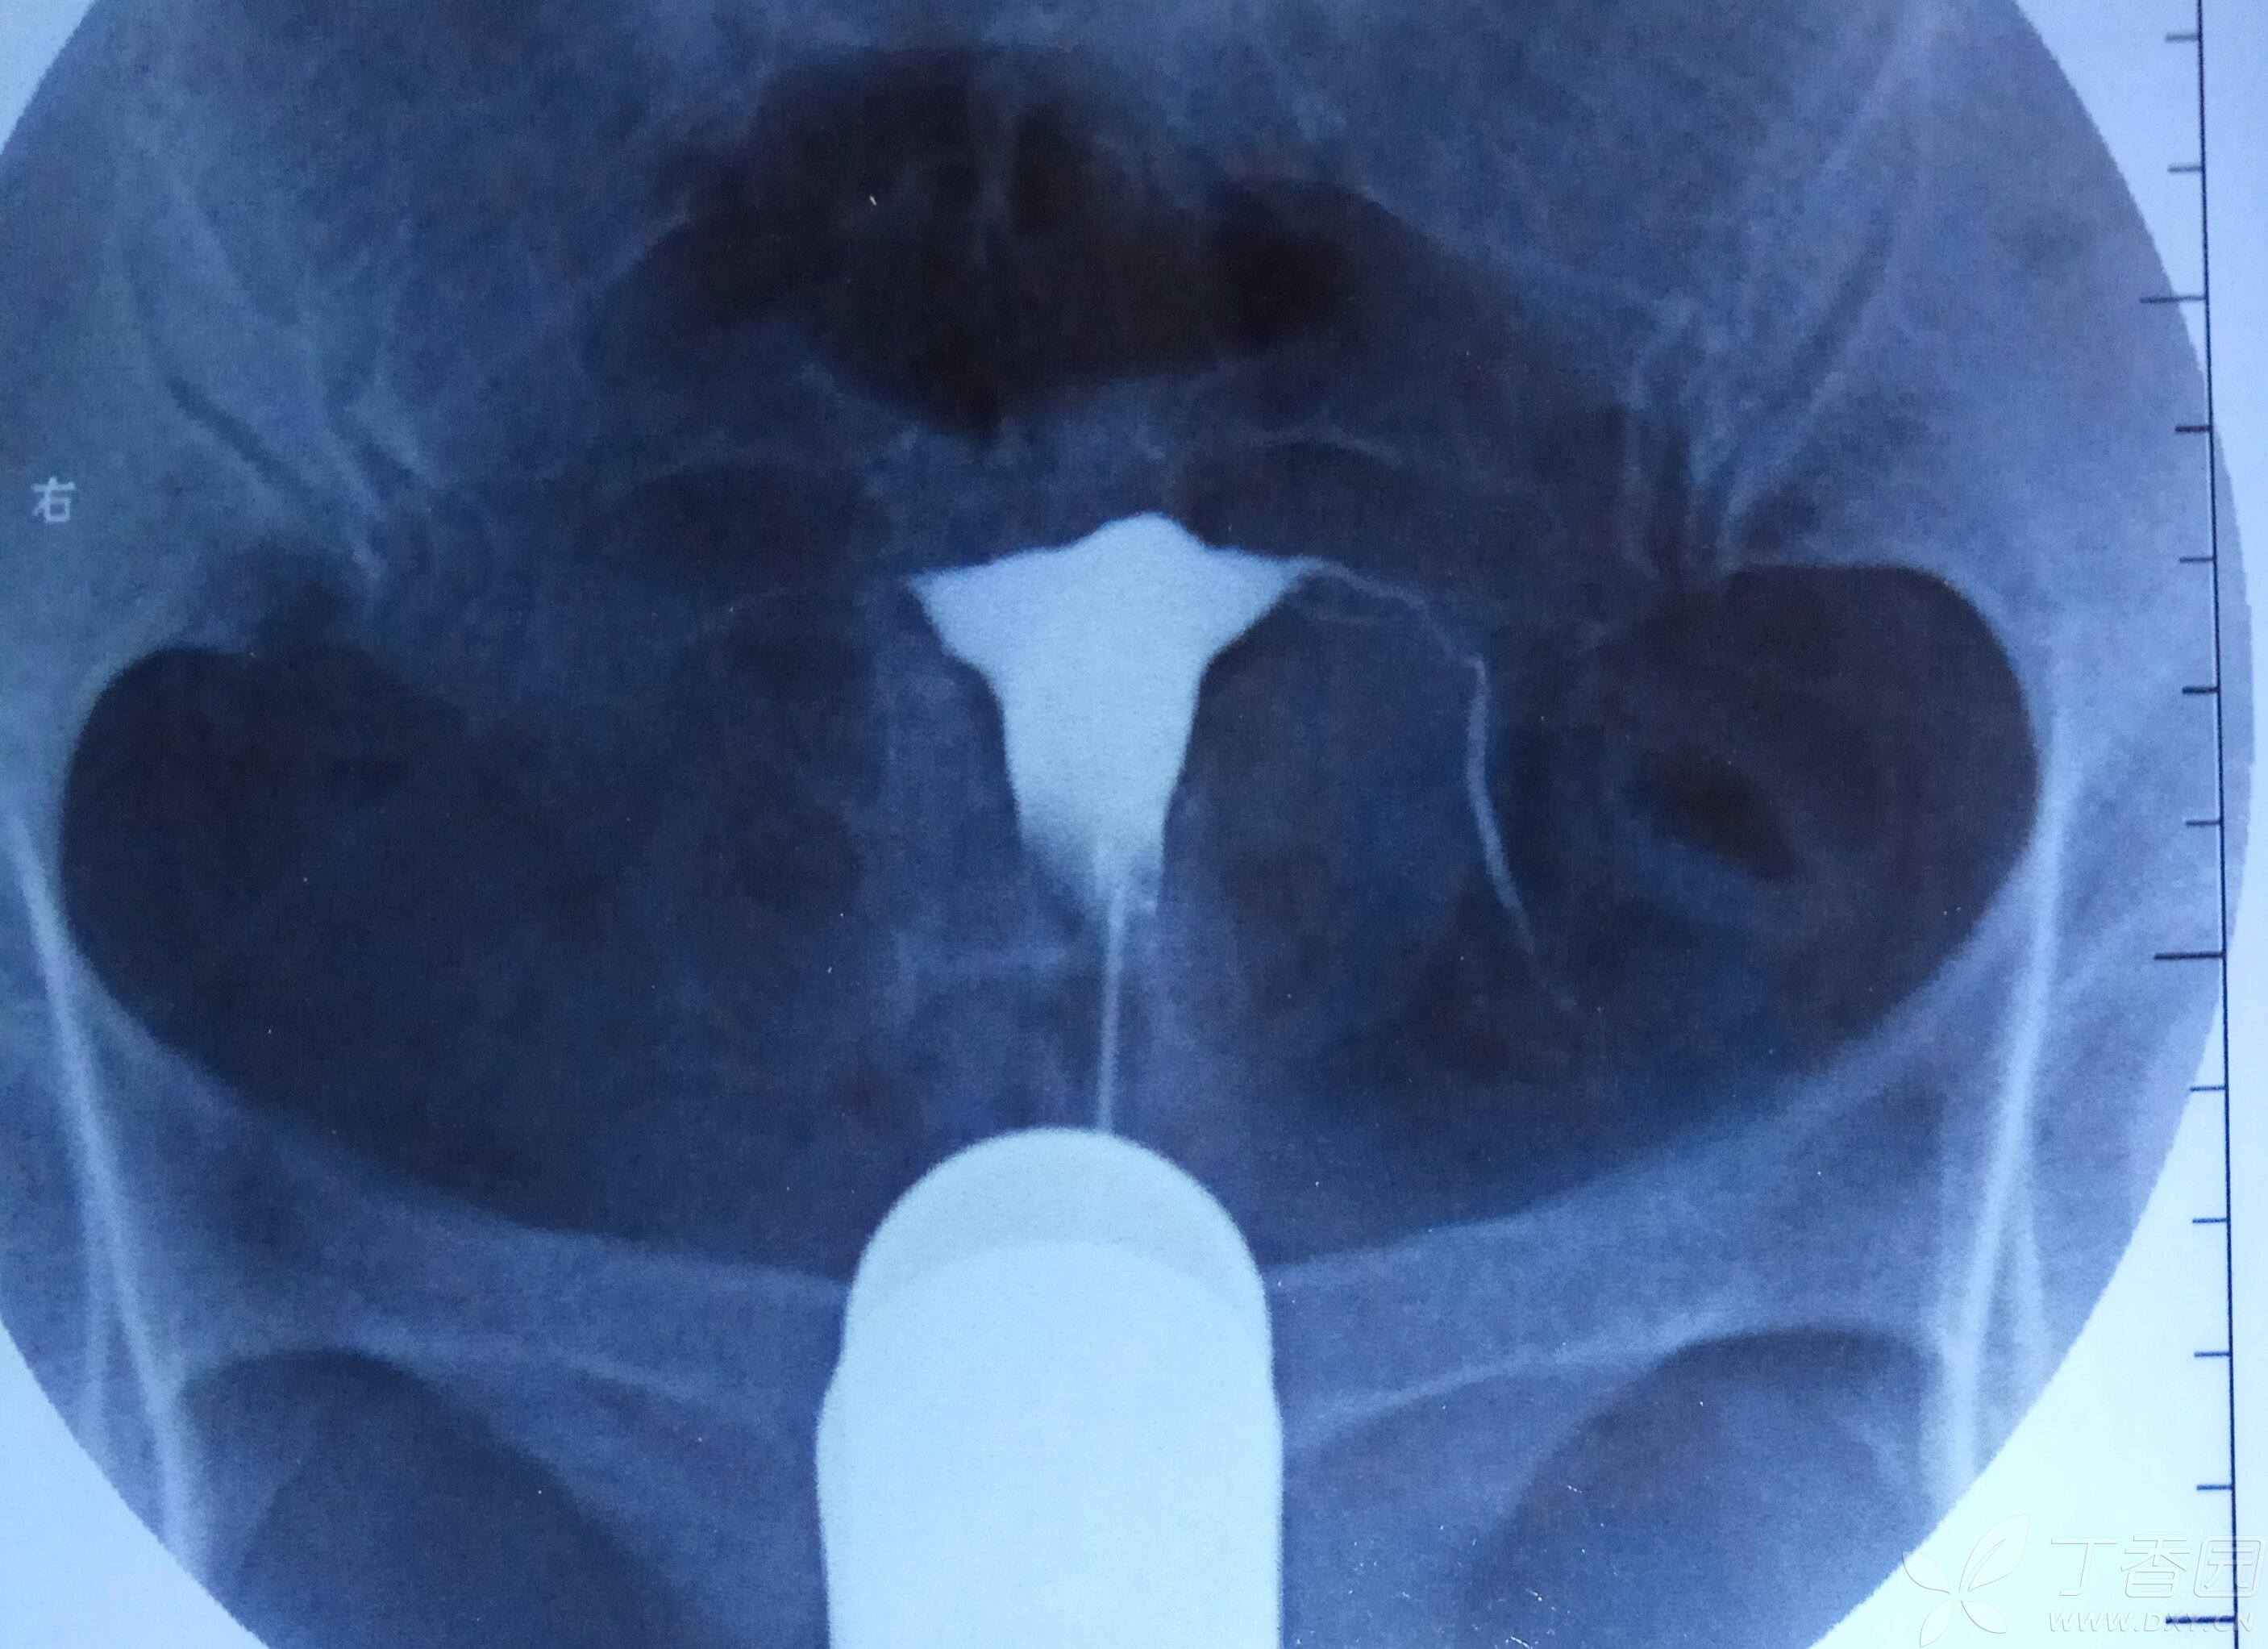

输卵管造影经X线的子宫输卵管造影是通过导管向宫腔及输卵管注入造影剂,利用X线诊断仪行X线透视及摄片,根据造影剂在输卵管及盆腔内的显影情况来了解输卵管是否通畅阻塞部位及宫腔形态的一种检查方法碘油造影常用40%碘化油国产30%乙碘油等碘水造影碘海醇或碘佛醇 对中枢神经的无明显毒性。

子宫输卵管造影是通过导管向子宫腔及输卵管注入造影剂,利用X线诊断仪行X线透视及摄片,根据造影剂在输卵管及盆腔内的显影情况,了解输卵管通畅性阻塞部位及子宫腔形态的一种检查方法检查目的评估输卵管通畅性通过观察造影剂在输卵管内的走行及弥散情况,判断是否存在堵塞粘连等异常这对于因输卵管。

输卵管造影是用来检查女性输卵管通畅与否的一种检测方法输卵管造影是临床上应用较为广泛的方法之一经X线的子宫输卵管造影是通过导管向宫腔及输卵管注入造影剂,利用X线诊断仪行X线透视及摄片,根据造影剂在输卵管及盆腔内的显影情况来了解输卵管是否通畅阻塞部位及宫腔形态的一种检查方法。